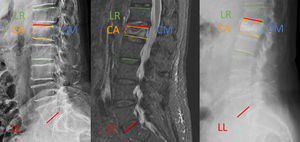

Antes de comenzar la cirugía se localizó y se marcó el nivel de fractura mediante fluoroscopio, así como la posición de los pedículos. La introducción del trocar en la vértebra se realizó siguiendo la técnica «hundir la flota» (fig. 1): se divide cada mitad del cuerpo vertebral en cuatro partes, en la proyección anteroposterior trazamos cinco líneas verticales (borde lateral del cuerpo; borde lateral del pedículo; mitad del pedículo; borde medial del pedículo y apófisis espinosa). Una vez dividido la mitad del cuerpo vertebral con cinco líneas en cuatro áreas las denominamos con las letras A (borde lateral cuerpo-borde lateral del pedículo), B (borde lateral pedículo-mitad del pedículo), C (mitad del pedículo-borde medial del pedículo) y D (borde medial del pedículo-espinosa).

De la misma forma se trazan cinco líneas verticales en la proyección lateral: borde posterior articular, borde posterior pedículo, punto medio pedículo, borde anterior pedículo y borde anterior cuerpo vertebral. Se delimitan cuatro áreas, que denominamos 1 (borde posterior articular-borde posterior pedículo), 2 (borde posterior pedículo-mitad del pedículo), 3 (mitad del pedículo-borde anterior del pedículo) y 4 (borde anterior pedículo-borde anterior cuerpo vertebral).

Usando esta terminología designamos la localización de la punta del trocar con una letra en la proyección anteroposterior y un número en la proyección lateral.

Recordando el tablero de hundir la flota podemos hacer una tabla de 5×5, en la que situamos las áreas en anteroposterior en la primera fila y las áreas en lateral en la primera columna. Para poder entender cuáles son las posiciones que corresponden a cada cuadrante podemos colocar una imagen de una sección coronal de la vértebra de la siguiente forma: la combinación de ambos caracteres nos dará tres posibles resultados, Pedículo: A1, B2, C3 y D4; Lateral: A2, A3, A4, B3, B4, C4, y Medial: B1, C1, C2, D1, D2 y D3. Con este sencillo método de coordenadas, mediante dos imágenes anteroposterior y lateral podemos localizar la punta del trocar en cualquier momento durante la canalización pedicular mínimamente asistida con escopia.

El análisis radiológico incluyó las pruebas de imagen preoperatorias (radiografías simples en proyecciones anteroposterior y lateral y resonancia magnética nuclear [RMN]) y las postoperatorias (radiografías simples en proyecciones anteroposterior y lateral en el primer día postoperatorio y radiografías en bipedestación o telerradiografías durante el seguimiento). Las mediciones realizadas en las imágenes radiológicas preoperatorias y postoperatorias fueron: Altura columna anterior (CA), Altura columna posterior (CP), Cifosis vértebra fracturada (CVF): medición del ángulo formado entre los platillos vertebrales, Lordosis regional (LR): medición del ángulo formado entre los platillos superior de la vértebra proximal y platillo inferior de vertebral distal, Lordosis Lumbar (LL): ángulo formado entre el platillo superior de L1 y el platillo inferior de L5 (fig. 2).

Parámetros radiológicos (fig. 2)La media de altura de la columna anterior (CA) antes de la cirugía era de 14,5mm y tras la cirugía de 20,9mm; habiendo una ganancia media de 4,7mm. Comparando ambos grupos no existen diferencias significativas.

La media de altura de la columna media (CM) antes de la cirugía era de 15,9mm y tras la cirugía de 21,5mm; habiendo una ganancia media de 6,1mm. En el grupo 1 la altura media de la CM antes de la cirugía era de 17,7mm y tras la cirugía, de 21,9mm; habiendo una ganancia de altura de 2,73mm. En el grupo 2 la altura media de la CM antes de la cirugía era de 15,8mm y tras la cirugía, de 25,9mm; habiendo una ganancia de altura de 8,3mm. Existe diferencia significativa entre ambos grupos. (p=0,05 [2,73-7,79]).

En el análisis de la cifosis (CV) destaca una disminución de la cifosis tras la cirugía de 3,5°. Comparándolo por grupos, en el grupo 1 el ángulo de cifosis se reduce 4,2° mientras que en el grupo 2, 3,09°. No hay diferencia significativa entre ambos grupos (p>0,05).

La lordosis lumbar (LL) tras la cirugía aumenta 3,5°. En el grupo 1 existe un aumento tras la cirugía de 5,45°. En el grupo 2 la LL aumenta 2,8°. No existen diferencias significativas entre ambos grupos (p>0,05).

La media de lordosis regional (LR) a nivel general antes de la cirugía es de 15,33° y tras la cirugía es de 16,54°, por lo que aumenta una media de 1,06°. En el grupo 1 la LR prequirúrgica es de 20° y posquirúrgica de 23,72°, aumentando una media de 3,25°. En el grupo 2 la LR antes de la cirugía es de 13° y tras la cirugía de 19° también existiendo una media de aumento de la LR de 5,9°. No existen diferencias significativas en la corrección de la lordosis regional.